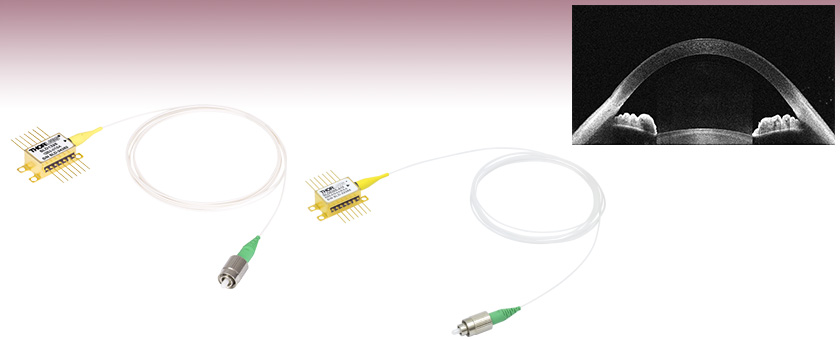

An Image of the Anterior of the Eye Taken with the SLD830S-A10 in a Modified Ganymede ll OCT System

SLD830S-A10

830 nm SLD, Gain Ripple: ≤0.15 dB

SLD830S-A10 (sold below) as a light source. The images each have an in-tissue depth of 6.2 mm and were taken using a 36 kHz A-scan rate.